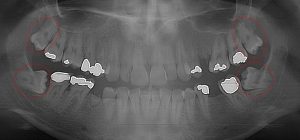

This 19 year old patient has all four 3rd molars present (circled). The roots are +90% formed. Both lower 3rd molars are impacted against the 2nd molars with no chance of further eruption and a +60% probability of decaying before age 30. The patient presented with pain and infection around both lower 3rd molars, requiring immediate extraction